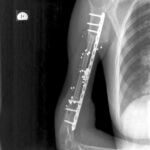

2.1. Учебная и клиническая база кафедры